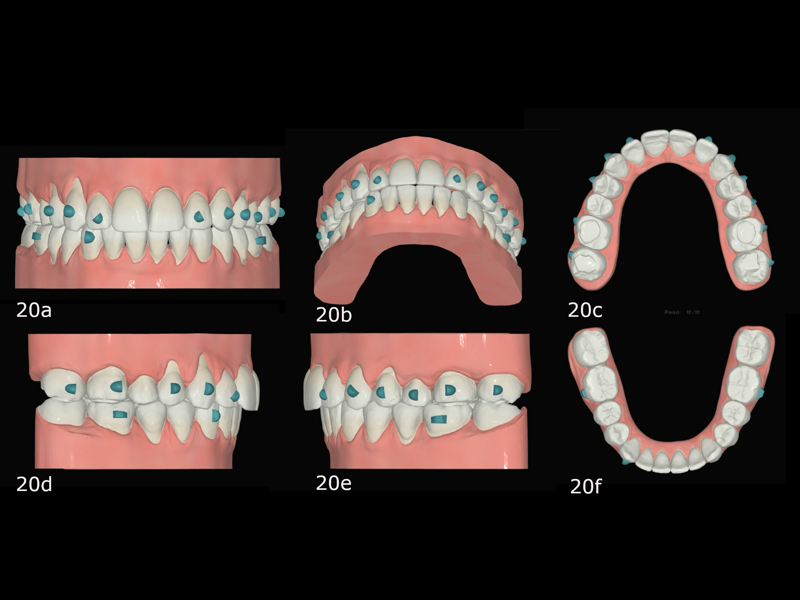

Initial treatment in 29 stages was planned, by which point the final occlusal results would have been obtained. We began with the placement of attachments and micro-screws in the maxillary arch for posterior intrusion (Fig. 18). After seven months of treatment and in the 20th stage, we introduced the FAS STOP and GO concept and took new records to prepare for the second phase of aligner treatment (Fig. 19). Thanks to STOP and GO, it is possible to achieve better tracking so that aligners fit properly and shorter treatment times using fewer aligners. This is the advantage of planning in different stages. It helps us achieve all our treatment goals on a consistent basis, and treatment efficiency is much higher.

The second phase of treatment began with the placement of new attachments (Figs. 20–22) and consisted of 12 stages, during which we continued to intrude the maxillary molars, centre the mandibular midline and level the occlusal planes. This phase lasted for four months. The total treatment involved 32 stages over 11 months, and all the treatment goals were achieved (Figs. 23–25).